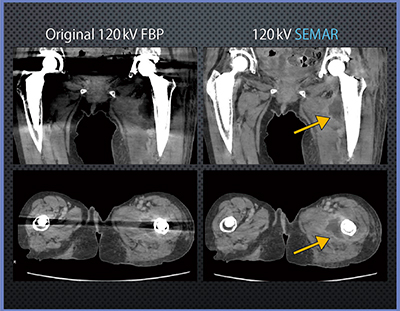

症例1は,THA術後左大腿深部膿瘍だが,SEMARでは人工関節のアーチファクトが抑えられ,膿瘍部分が明瞭に描出されている(図5)。

図4 人工関節コンポーネントとDVT模擬ファントムによる

DEとSEMARの効果比較

図5 症例1:THA術後左大腿深部膿瘍